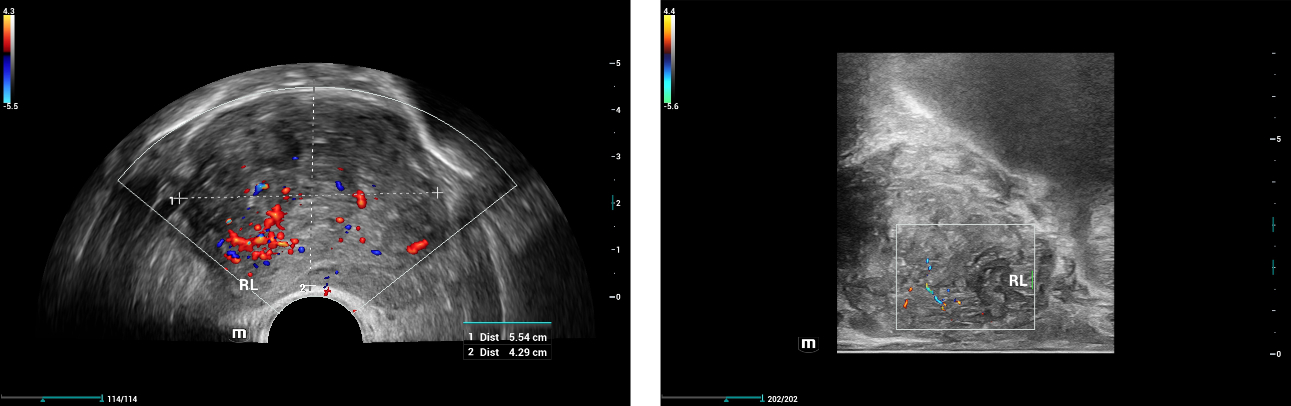

2D and Color Ultrasound findings:

Due to its anatomical location, it is recommended that a prostate ultrasound examination be conducted using real-time transrectal ultrasound (TRUS) with the highest frequency biplane endocavitary transducer (Mindray Resona i9, ELC13-4)

Prostate scanning was performed with a Mindray dedicated biplane convex-linear ultrasound probe. The transducer contains 2 ultrasound probes: the convex array and the linear array. The transverse image of the prostate was obtained with the convex array and the longitudinal image of the prostate was obtained with the linear array. Convex and linear arrays were supported with both Elastography techniques including: Strain Elastography (NTE, Natural Touch Elastography) and 2D Shearwave Elastography (SWE, Sound Touch Elastography).

Ultrasound Findings of rigth lobe of the prostate:

2D and Color Ultrasound showed a suspicious hypoechoic area in RL with hypervascularity and capsule-irregularity, but the LL findings were normal with just a bit uneven capsule, which made us confused whether the PCa happened on the whole prostate in both sides RL and LL or it just happen on the RL as RL has some typical findings of PCa.